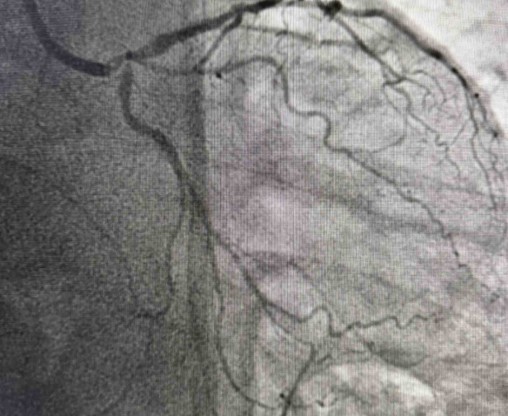

Tokom dva dana u angio sali izvedene su i izuzetno složene intervencije na koronarnim arterijama srca, uključujući perkutane intervencije na hronično - potpuno zapušenim krvnim sudovima srca i intervencije na tzv. glavnom stablu (left main) koja je glavna artrija srca i čije liječenje takođe spada u veoma rizične zahvate u interventnoj kardiologiji.

Još jedan slučaj koji izdvajamo kao posebno složen je bio kod pacijenta O.M (81), kod kojeg je dijagnostikovana teška trosudovna koronarna bolest.

„Pacijent je imao simptome angine pectoris. Nakon urađene koronarografije verifikovana je teška trosudovna koronarna bolest, gdje su bolesne bile desna koronarna arterija, dok je na lijevoj strani kritično mjesto bilo na glavnom stablu  odakle ide račvanje u dvije grane. Takvi pacijenti uglavnom završavaju na kardiohirurškom konzilijumu i na operaciji bajpasevima. Međutim, odluka konzilijuma u Banjaluci je bila da se, zbog godina života pacijenta,  radi perkutana intervencija na desnoj i lijevoj koronarnoj arteriji uključujući glavno stablo.Takve procedure zahtijevaju da se rade sa kontrolom imidžinga, savremene intravaskularne dijagnostike (IVUS), što smo mi i uradili. To dodatno povećava bezbijednost i preciznost zahvata. Procedura je trajala svega 45 minuta, a pacijent je već narednog dana otpušten kući“, izjavio je dr Janjičić.

Tim interventnih kardiologa JZU Bolnica „Sveti Vračevi“ Bijeljina je od 2020. godine izveo više od 100 intervencija na glavnom stablu (left main).